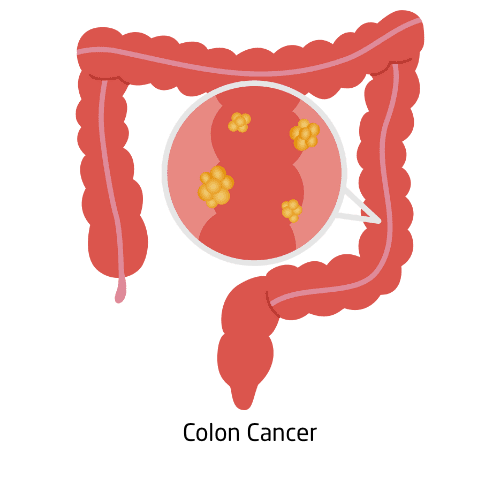

Colorectal cancer develops in the colon or rectum, often starting as small polyps that may become cancerous over time. It’s one of the leading causes of cancer-related deaths but is highly treatable when found early through screenings like colonoscopy or stool tests. Common symptoms include changes in bowel habits, blood in the stool, abdominal pain, and unexplained weight loss. Risk factors include age, diet, family history, and lifestyle choices.

Treatment options typically include surgery, chemotherapy, radiation, and targeted drugs. A healthy diet, physical activity, and regular screenings are key in prevention and long-term wellness.